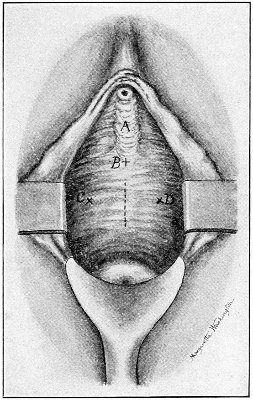

Fig. 2.—Bimanual examination.

Fig. 3.—Bimanual examination; median sagittal section of the pelvis.